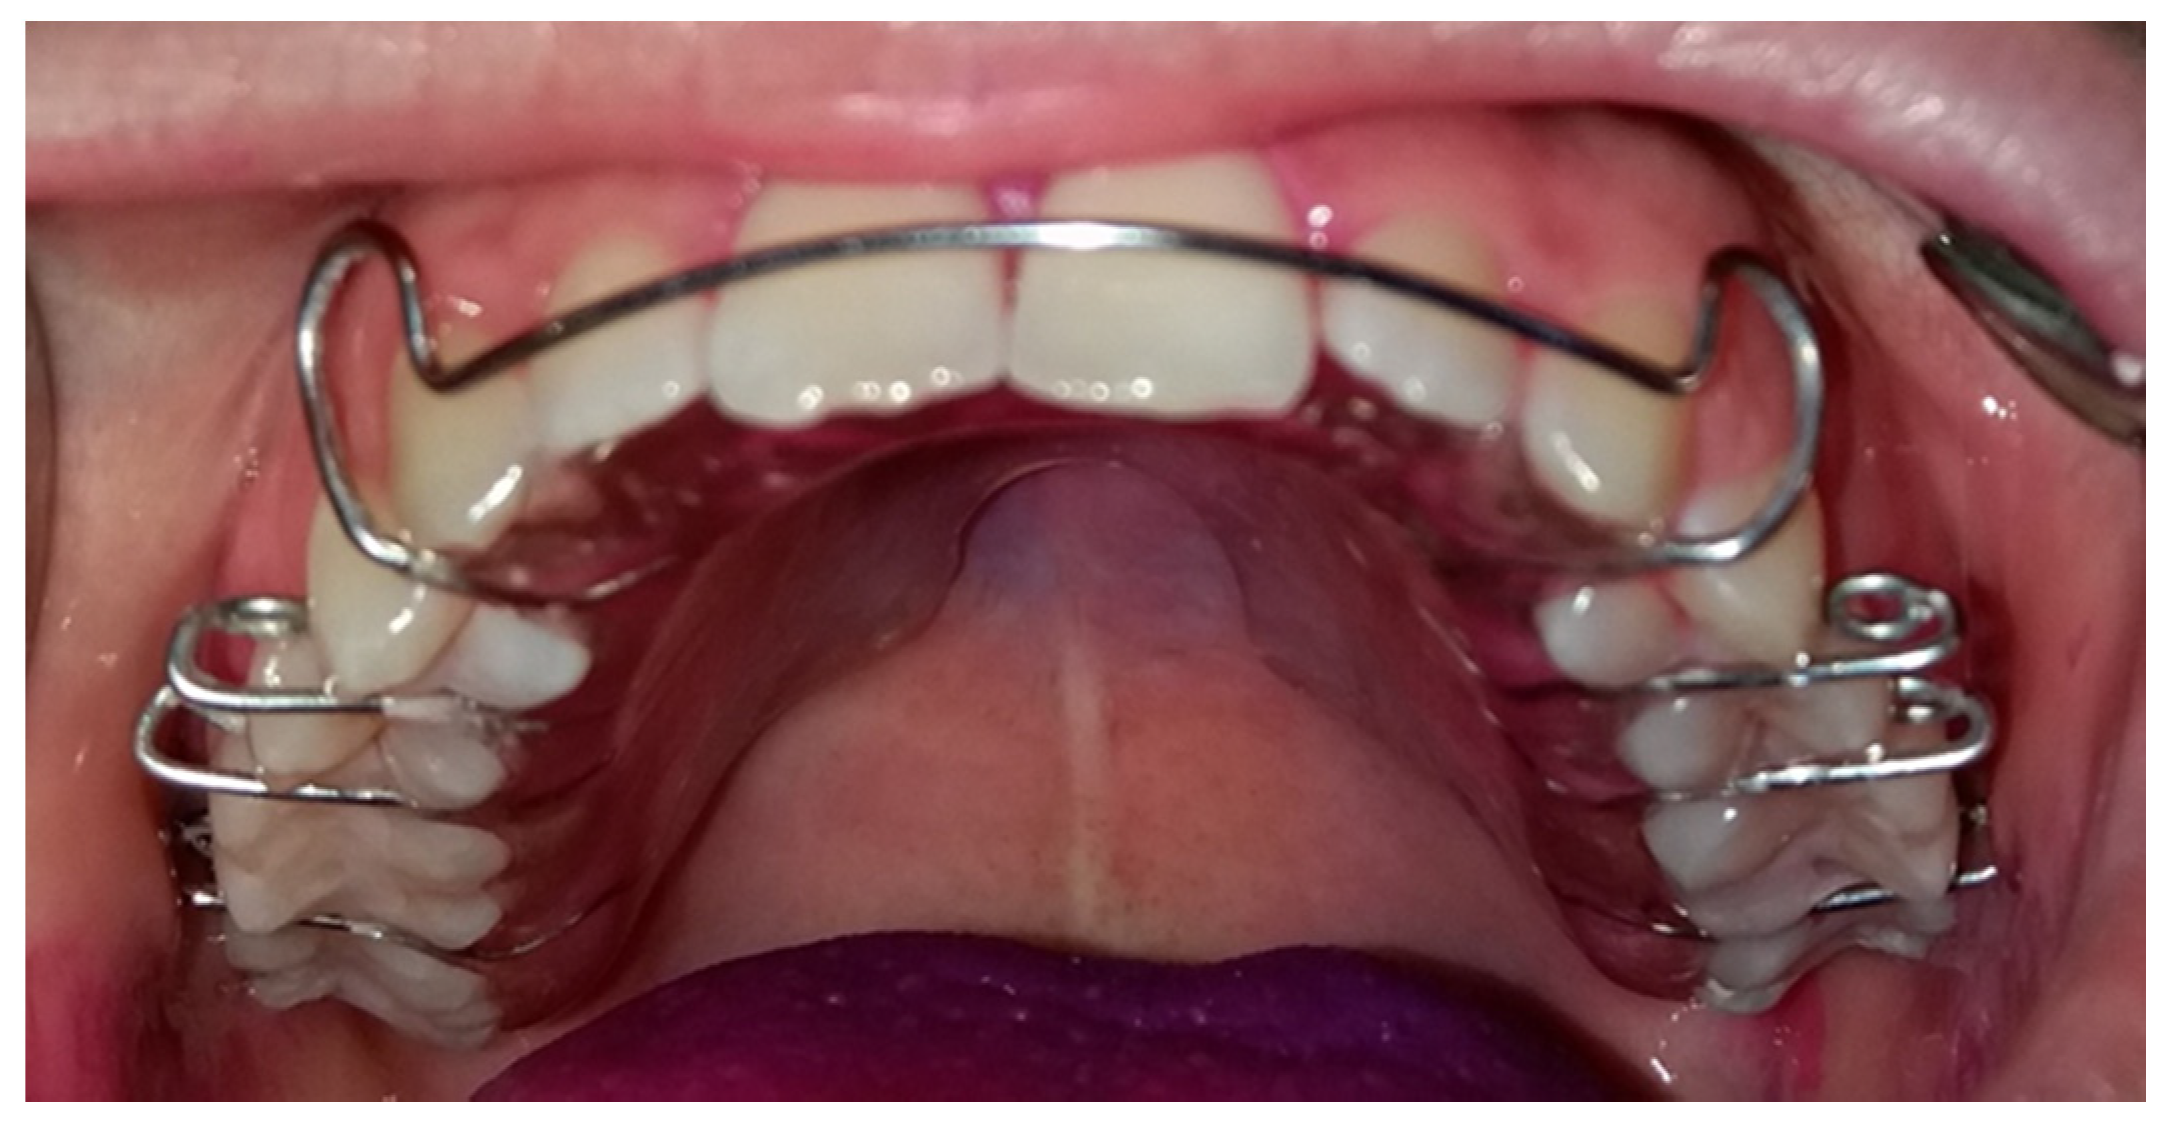

The Hawley retainer designed by Charles Hawley in 1920 (Figure 1) has proven its effectiveness for more than a century. Along with the retention, it can also be an active orthodontic instrument which, through the action of mechanical forces, produces small changes such as the closure of the remaining interdental spaces due to the anchoring by the orthodontic rings [18].

Figure 1. Hawley retainer used in the study.